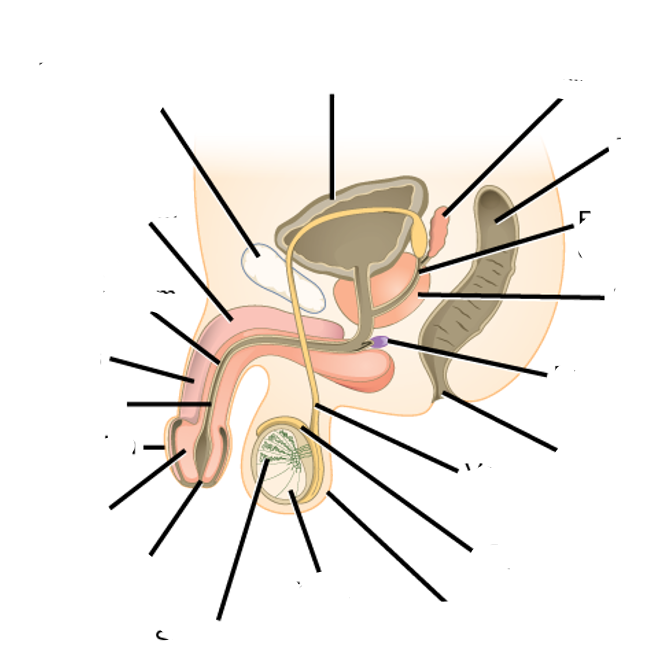

what is this image showing